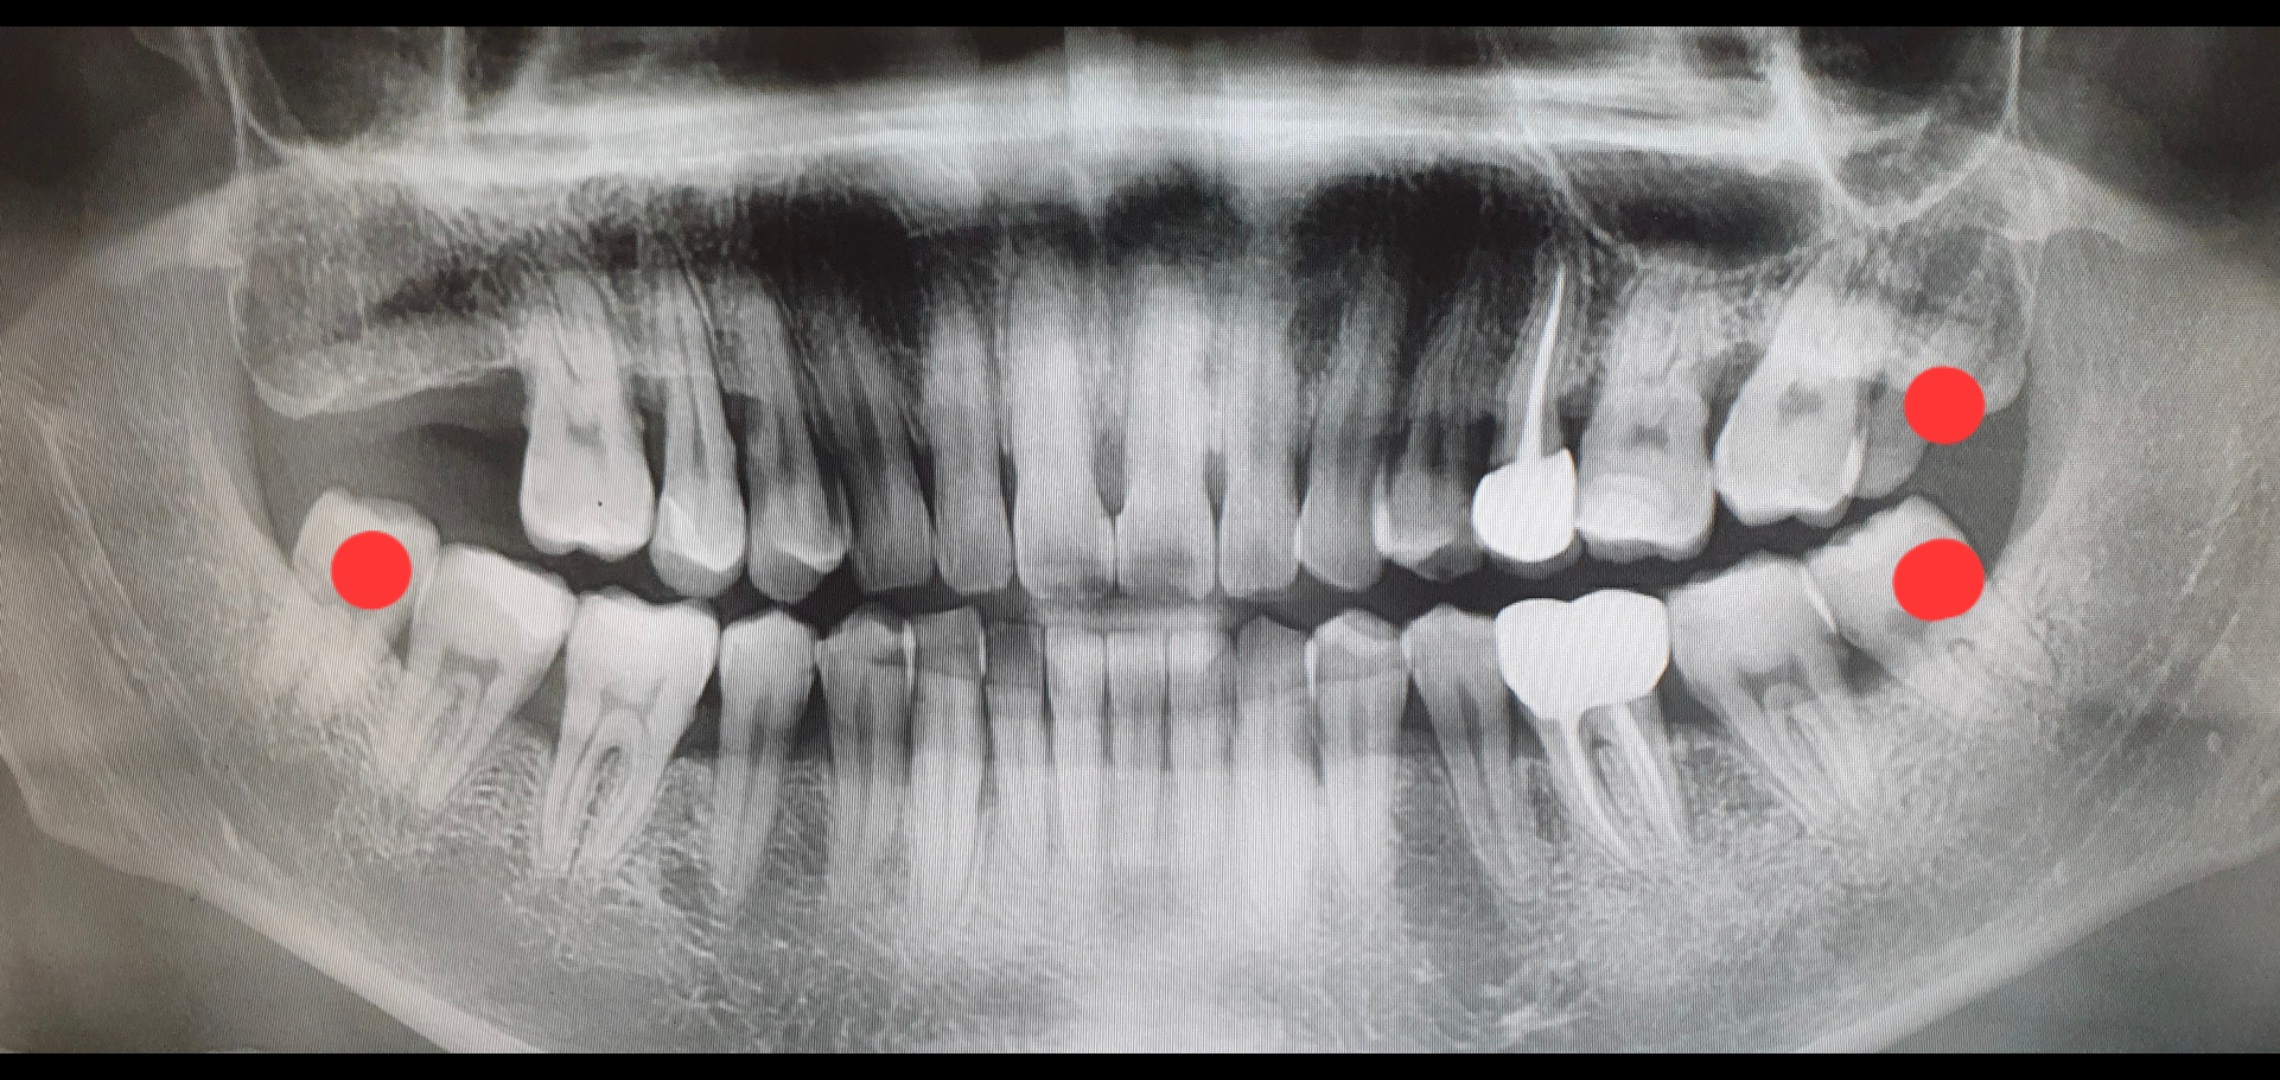

치과 체어에서 대기하는 동안

내 앞의 모니터에 떠있는 내 엑스레이(CT?) 사진을 폰으로 찍었다.

빨간 점으로 표시한게 사랑니들이다. 오른쪽 2개는 며칠전 뽑아서 잘 아물고 있고,

다음주 목요일에 왼쪽 남은 하나를 마저 뽑을 예정이다.